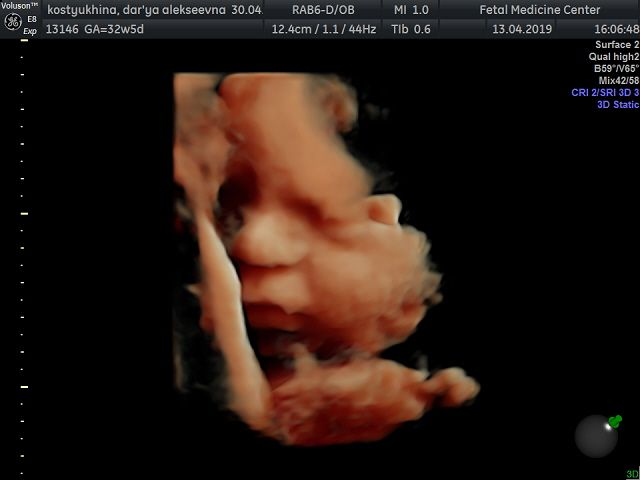

Вот и добралась до флешки))) Наш сыночек в цвете ? смотрю и не верю!!! Какое же чудо природы, да и техники фото через органы? еще 1,5 мес и состоится встреча всей жизни ? Вчера после скрининга зашли в кафе израильское, малыш ликует от этой пищи!!! С собой взяли паштет из тунца с кедровыми орешками и сушеной клюквой, села кушать и снова танцы ? блин даже от сладкого такого нет ? А что любят ваши малыши?)